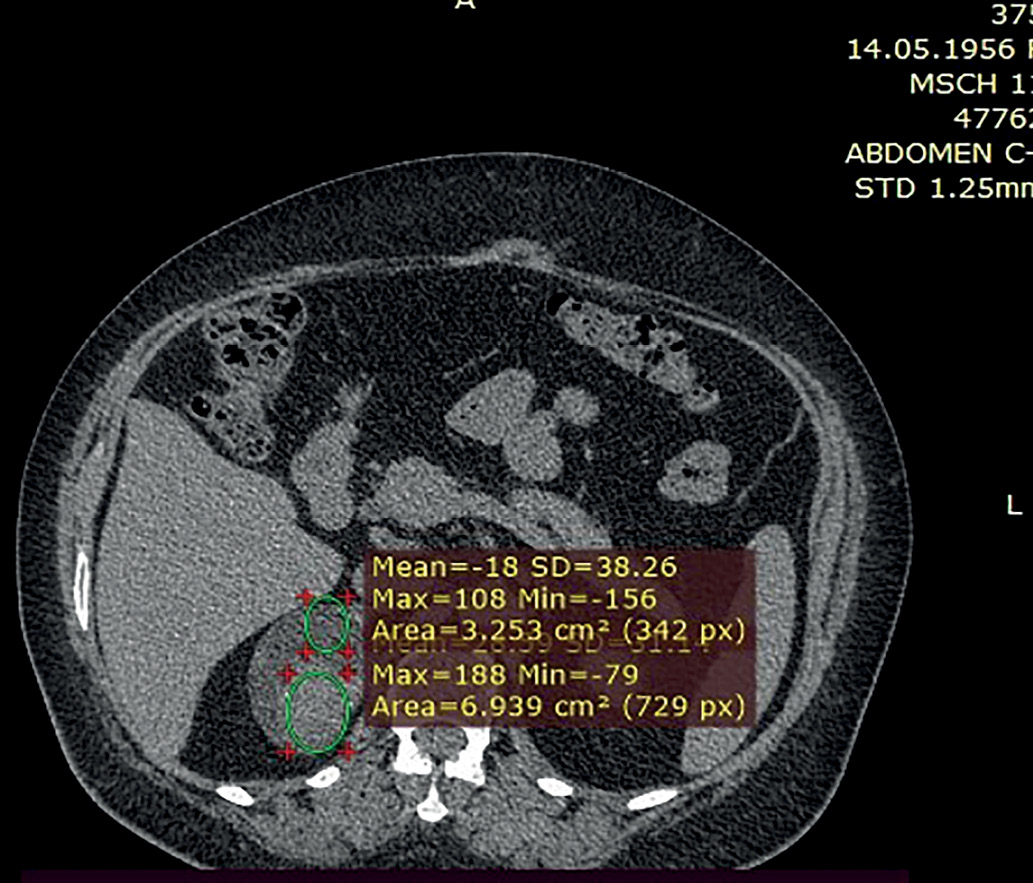

1. Рис. 1. КТ, венозная фаза. Опухоль имеет гетерогенную плотность. | |